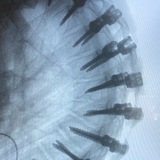

Молодой человек, 16 лет. Врожденная мобильная деформация пальцев стопы.

На плантограмме определяется только четыре пальца: второй палец накладывается на первый и третий.

Такую деформацию можно корректировать с помощью тейпов, однако мама пациента отметила, что он не будет регулярно их использовать.

Поэтому было выполнено индивидуальное ортезирование: с помощью тейпов зафиксировано оптимальное положение пальцев и произведена формовка силиконовой пасты. Данные изделия помогают скорректировать деформацию в том числе в обуви